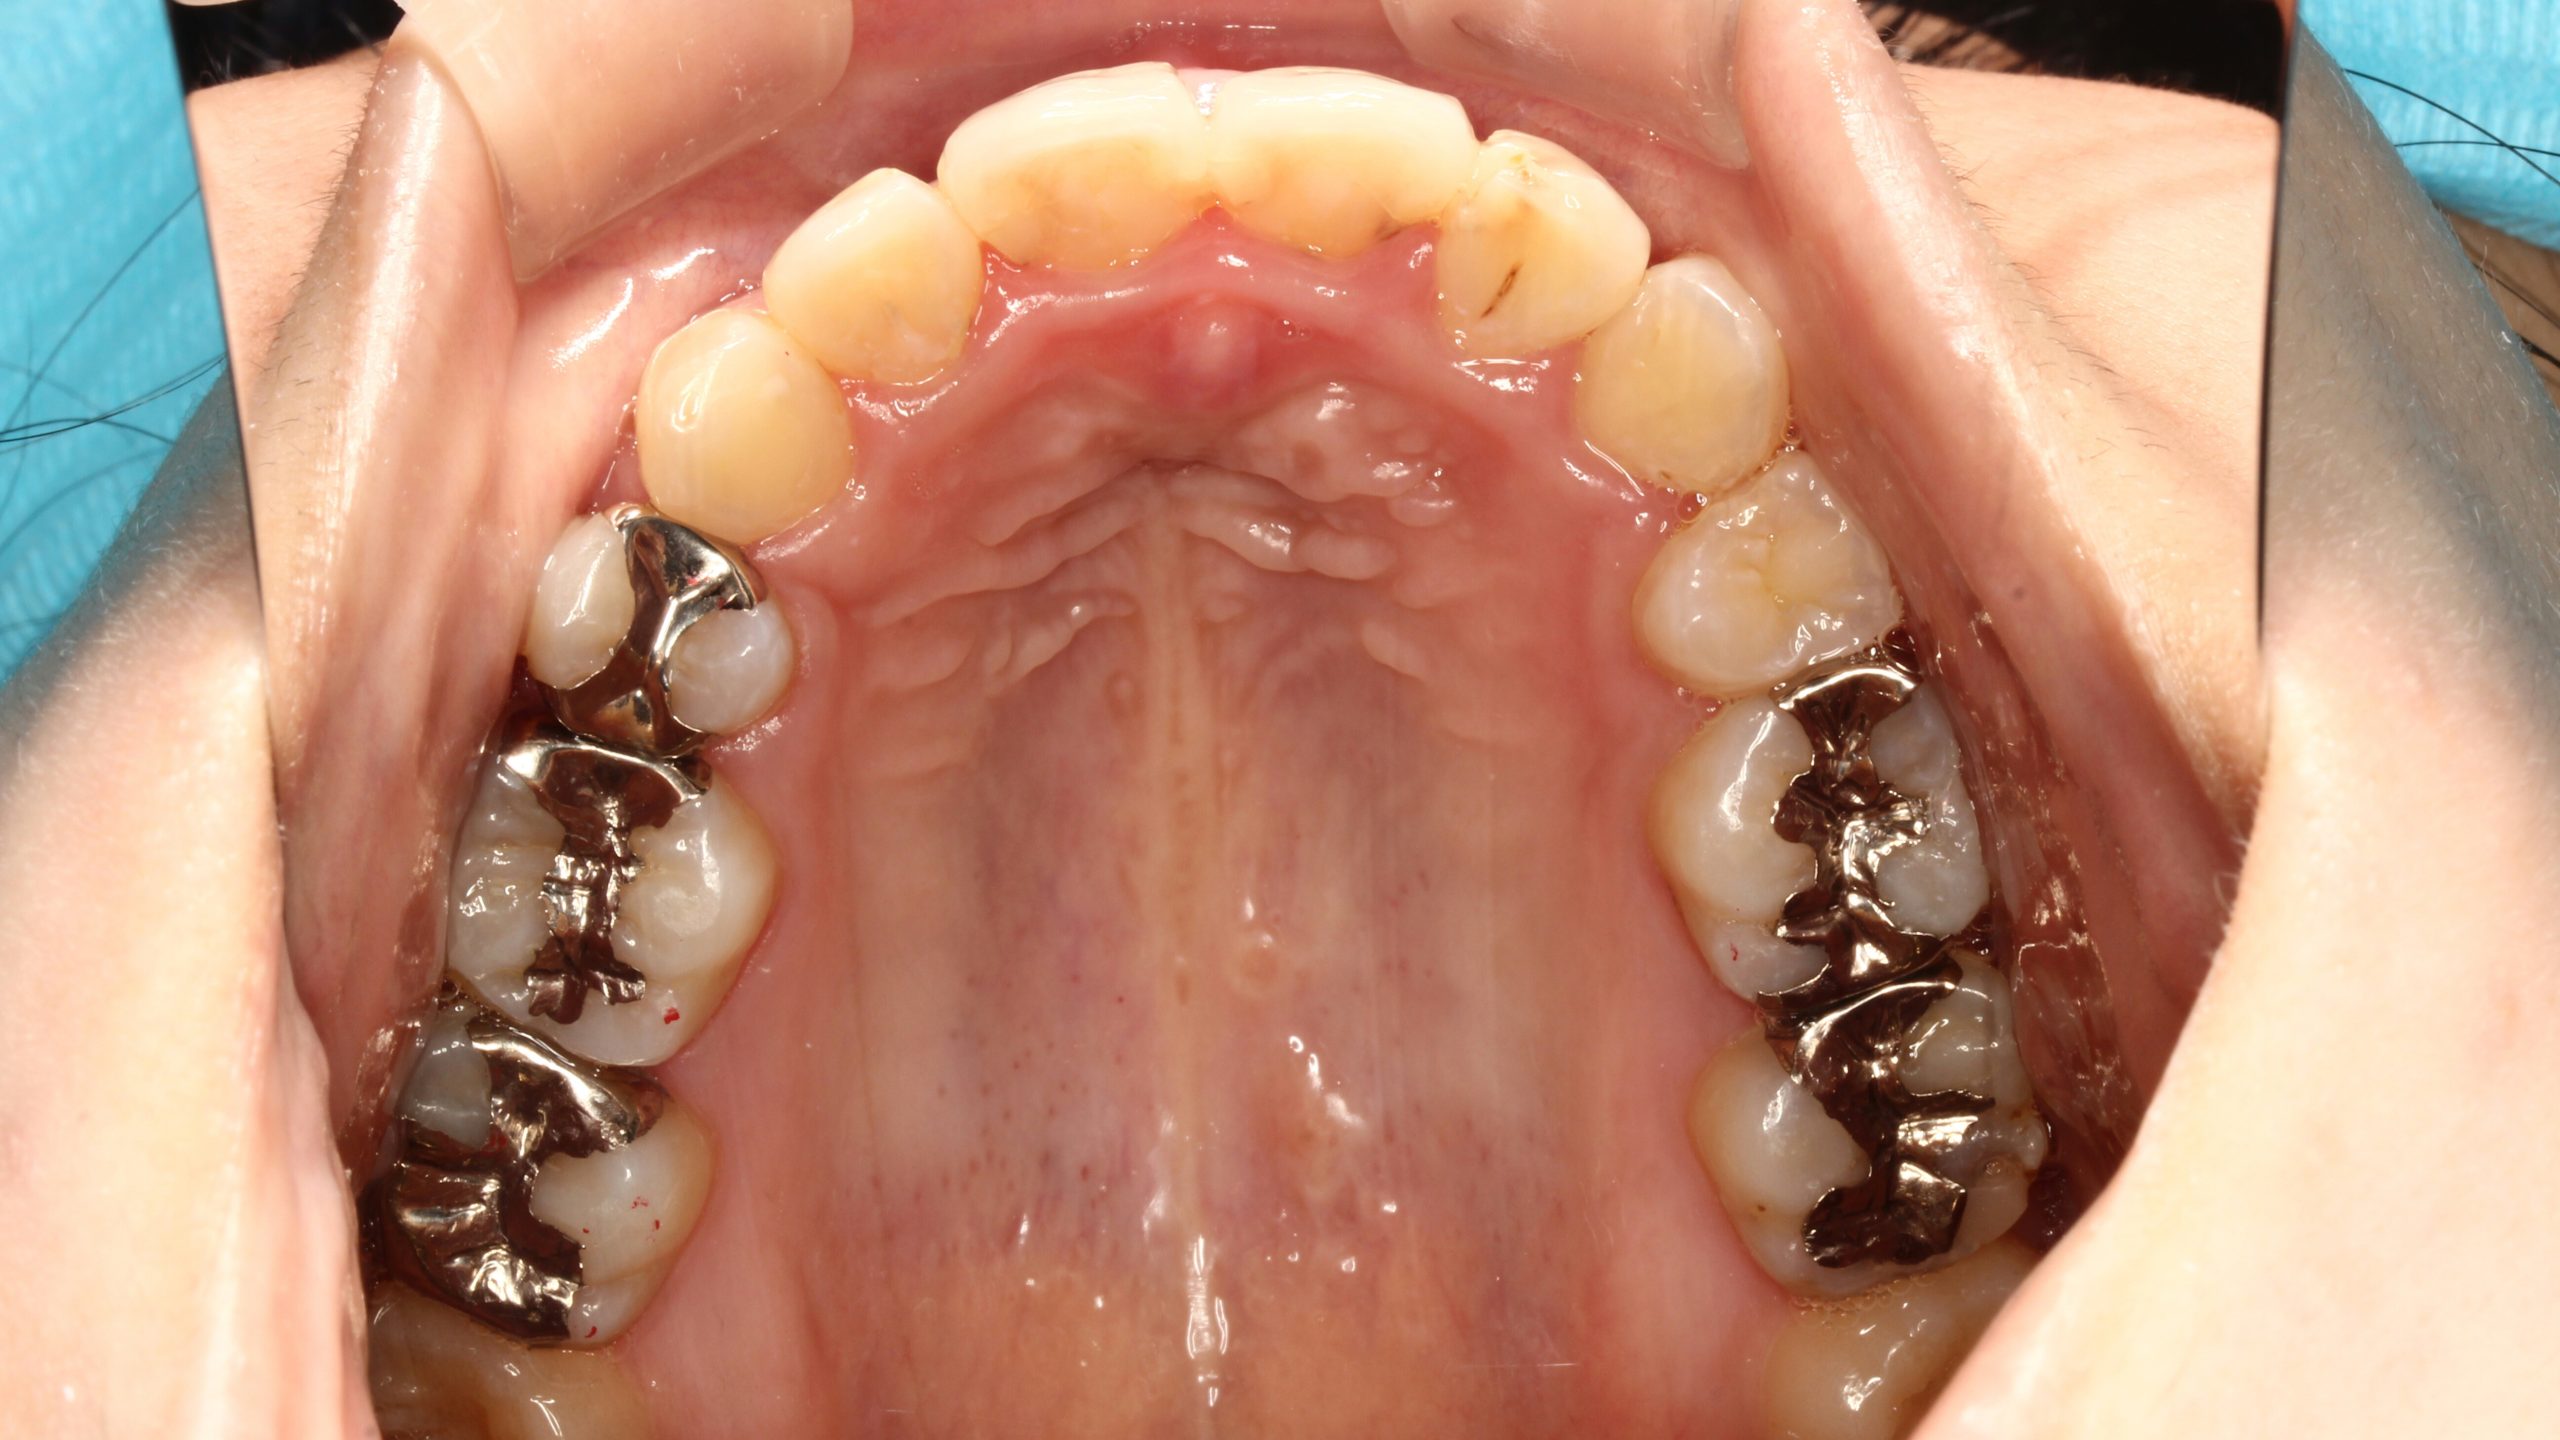

下の歯が出ている ・噛んだ時に、下の歯と上の歯がかみ合わない

| 主訴 | 下の歯が出ている ・かんだ時に、下の歯と上の歯がかみ合わない |

Before